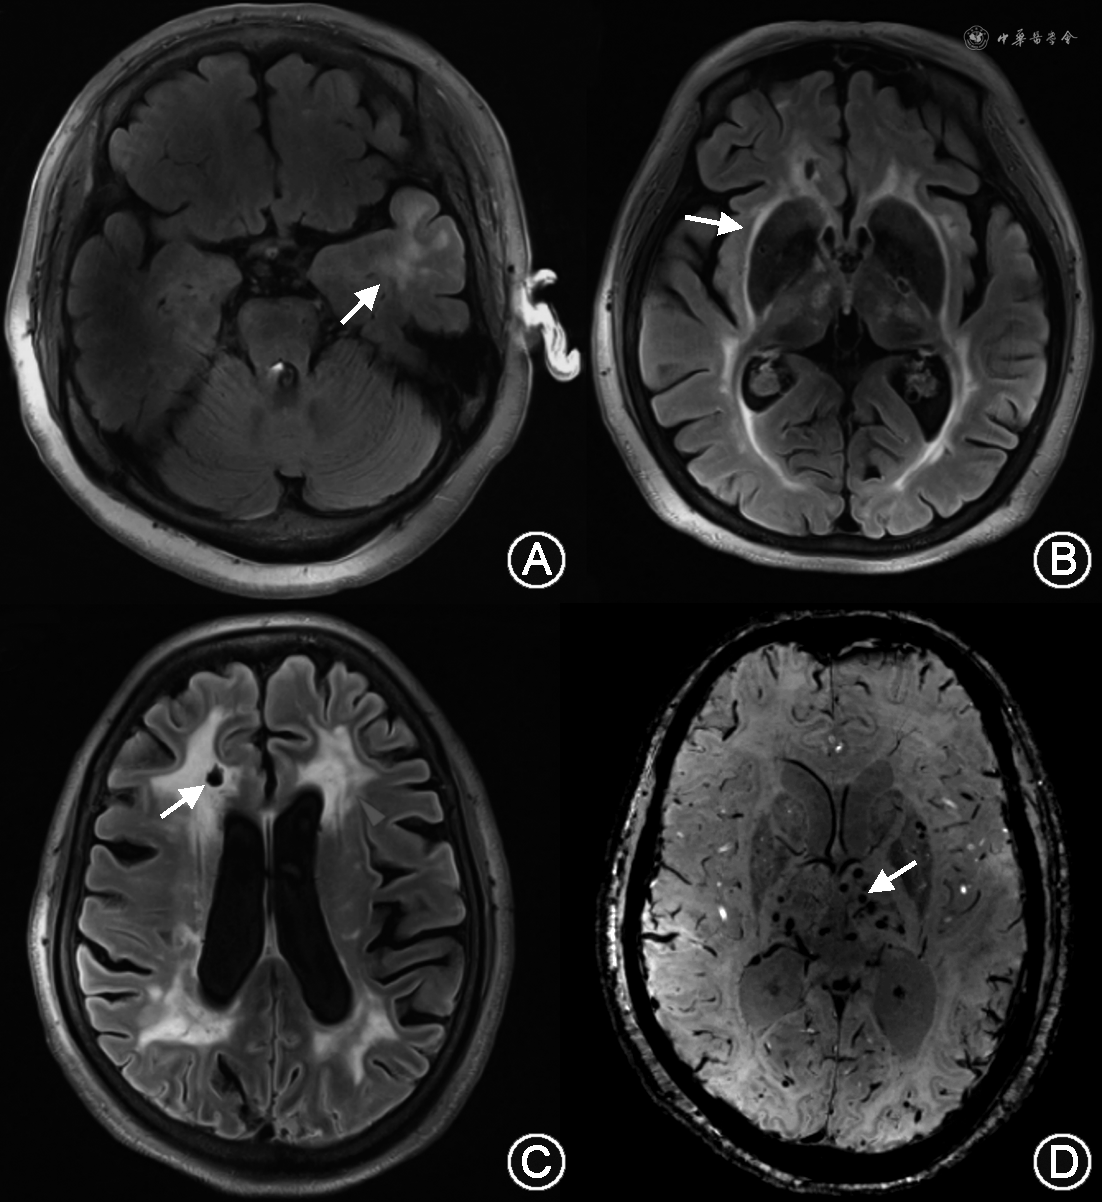

MRI检查包括常规头颅平扫序列和微出血扫描序列,其改变包括(图2):(1)脑白质高信号(white matter hyperintensities,WMHs)是患者最早和最常见的影像学改变,35岁之后基本上所有的CADASIL患者都会有不同程度的WMHs[18],分布在脑室周围白质、颞极、外囊、额顶区白质,U形纤维通常不被累及[19]。一项小样本研究结果表明,颞极白质高信号区别CADASIL和散发脑小血管病的敏感度和特异度分别为90%和100%[20],但亚洲患者颞极受累比例较欧美患者低。WMHs的发生原因与血脑屏障破坏导致的白质水肿以及白质纤维束的病变有关。(2)腔隙性脑梗死(lacunar infarctions,LIs)是患者另一常见的影像学表现,出现在几乎所有疾病晚期的患者中,主要分布于半卵圆中心、丘脑、基底节和脑桥。LIs与WMHs有一定的相关性,Duering等[21]发现大约90%的LIs出现在WMHs的边缘,仅5.8%出现在WMHs中或WMHs以外,提示LIs与WMHs是同一疾病动态发展过程中的不同表现。越来越多的研究结果提示,CADASIL患者的LIs不是由穿通动脉的闭塞造成,而可能与血流动力学改变导致的局部低灌注有关,对CADASIL患者进行7.0 T MRI检查也提示其基底节的病变可能并不是由豆纹动脉的闭塞造成[22]。(3)脑微出血(cerebral microbleeds)出现在约50%的我国患者当中,主要分布在深部脑区。脑微出血数量与患者的年龄和MRI总病灶负荷呈正相关,高血压与脑微出血的发生独立相关,脑微出血负荷(微出血数量≥9个)与脑出血的发生独立相关[23]。(4)血管周围间隙(perivascular space)的扩大可出现在78%的患者中,主要位于颞叶、基底节和皮质下白质,其严重程度随患者的年龄增长而增加,颞叶或岛叶下区扩大的血管周围间隙的严重程度与患者脑白质高信号的严重程度密切相关[24]。由于CADASIL患者多无明确的血管狭窄和闭塞,脑血管造影不推荐,个别研究报道血管造影可能会增加患者神经系统并发症的风险[25]。